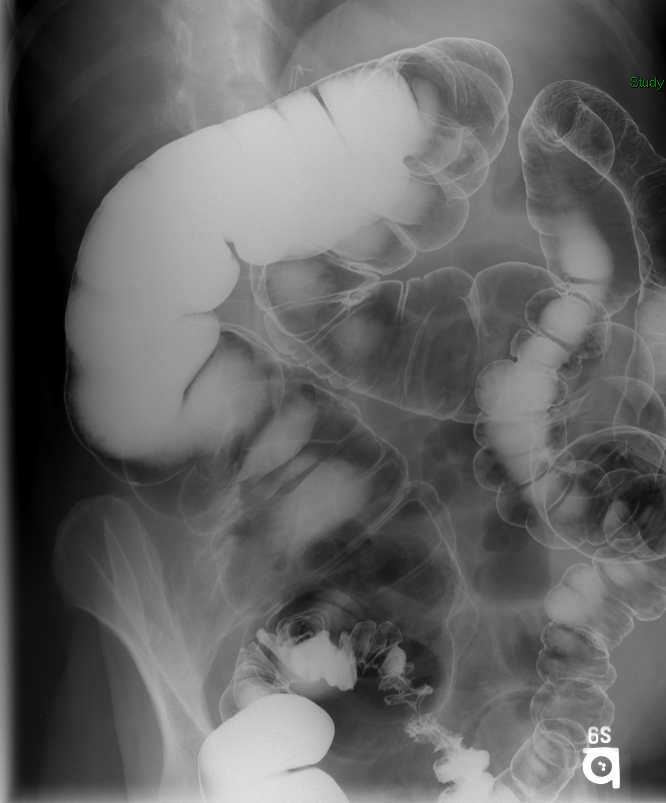

- Once 15 minutes has passed since the patient drank the barium, the technologist will obtain a prone (if possible) radiograph

(key image 2).

- Prone positioning is preferred because while lying prone, the weight of the body provides compression of the bowel loops.

- The film should include the entire stomach as well as the bowel that is filled with contrast.

- The technologist will obtain radiographs at 30, 45, and 60 minutes after the initial administration of barium. If the column of contrast material has not reached the large bowel on the 60 minute film, the technologist will obtain images every 30 minutes until contrast can been seen in the cecum

(key image 3)

(key image 4)

(key image 5).